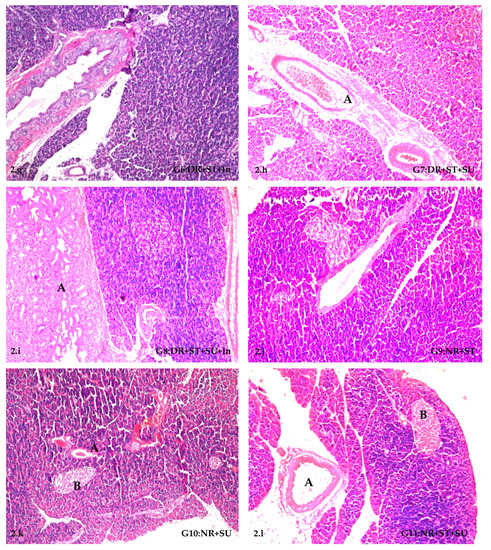

2.5. Histopathological Alterations in Pancreases of STZ-Induced Diabetic Rats

| Experimental Group | Atrophy of Islands of Langerhans | Absence of Langerhans Cells | Ductal Hyperplasia | Newly Formed Ductules |

|---|---|---|---|---|

| NR | − | − | − | − |

| STZ-DR | +++ | +++ | +++ | +++ |

| DR+SU | +++ | +++ | ++ | ++ |

| DR+SU+In | ++ | + | ++ | ++ |

| DR+ST | + | − | − | − |

| DR+ST+In | − | − | − | − |

| DR+ST+SU | +++ | +++ | − | − |

| DR+ST+SU+In | ++ | − | + | ++ |

| NR+ST | − | − | − | − |

| NR+SU | + | − | − | − |

| NR+ST+SU | − | − | − | − |